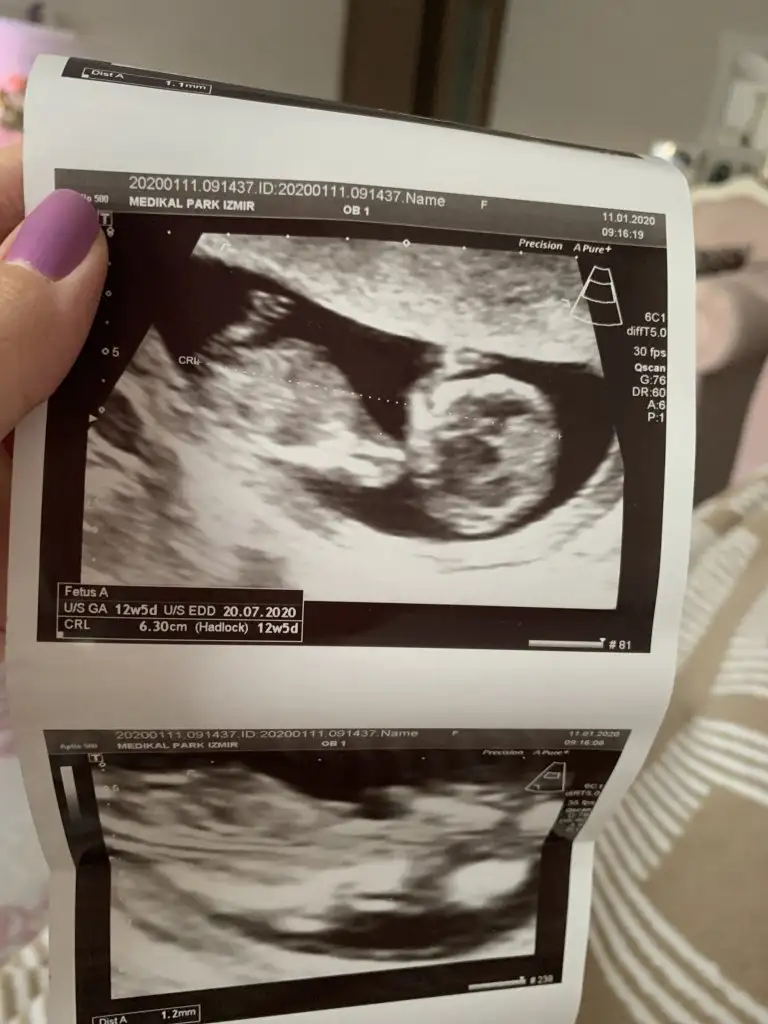

Net olmamakla birlikte kız siz yinede 12 haftayı paylaşın usg net degilTeyzeleri bize bakabilir misiniz acaba cinsiyet ne ola ki 11. Haftaya gireceğiz![]()

Kız gibi 12 haftayı paylaşın

Nubu biraz kapatmış bacagı ama sanki erkek gibi başka usg varmı 11 hafta yada 12+4 den başka usgMerhabalar ben de çok araştırdım bu teoriyi kız gibi geldi bana ama sizce nedir 12+4 ten ultraEki Görüntüle 2577076 Eki Görüntüle 2577077 son

Nubu kapalı görünmüyor başka usg varmı sanki eminde değilim kız gibi

Teşekkür ederim. Hayırlısı sağlıklı olsun inşallah. Doktora da sordum da bakti epey hic fikir yürütemiyorum dedi hangi resme göre yorumladınız birinde sırtı dönük gibi. Yanılıyor muyum?Arada kaldım yüzde altmış kız yüzde kırk erkek